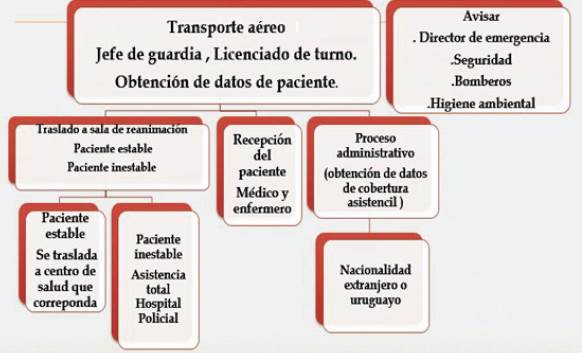

La asistencia de estos pacientes requiere de equipos especializados y entrenados en la toma de decisiones en todo el proceso de la cadena asistencial: estabilización, transporte y recepción (Figura 4).